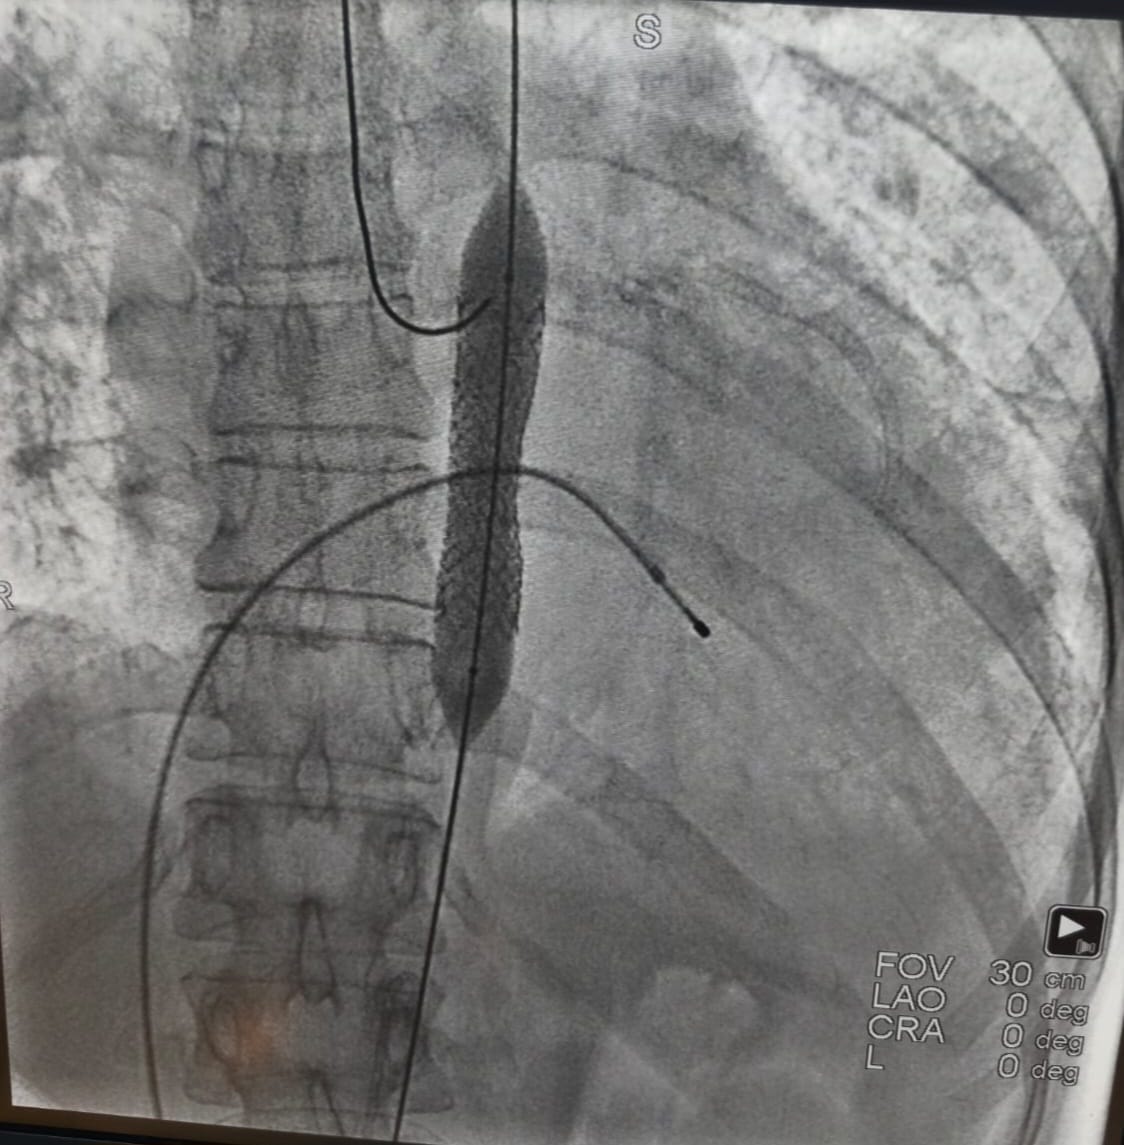

Acil servise başvurmasının ardından hızla anjiyografi ünitesine alınan hastanın işlem sırasında kalbi durdu. Kardiyoloji ekibinin anında müdahalesiyle tıkalı iki damar açılarak kalp ritmi yeniden sağlandı. Ancak aort damarındaki ciddi darlık nedeniyle tansiyon kontrol altına alınamayınca ve solunum sıkıntısı devam edince, endovasküler (kapalı) yöntemle aort koarktasyonu tedavisi uygulanmasına karar verildi.

Gerçekleştirilen ileri düzey girişim sonrasında hastanın tansiyon değerleri normal seviyelere dönerken, nefes darlığı da büyük ölçüde geriledi. Yaklaşık 10 gün süren yoğun tedavi ve takip sürecinin ardından hasta sağlıklı şekilde taburcu edildi.